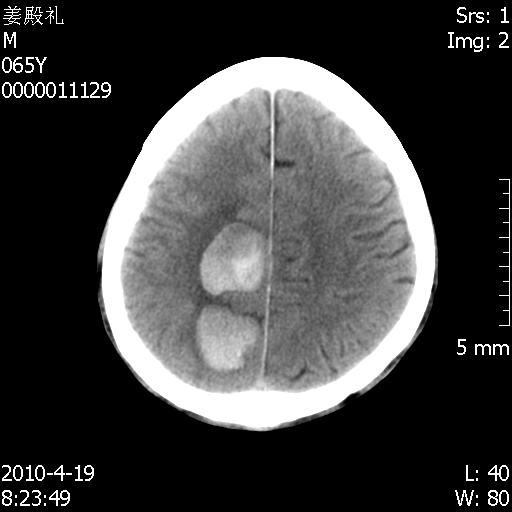

老年男性,突发左下肢无力1天,其余有价值的检查都没有。平扫ct值大约60hu,增强后ct值没什么改变,请大家讨论一下这个病例是什么?说明诊断理由。

左小脑、右大脑顶叶多发圆形高密度病灶,其周环状低密度影。考虑多发脑出血。隔期观察。

至于是出血还是微小钙化所致的高密度无法考证,三个都出血也不是一点都不可能,同一种组织学类型的肿瘤受到同一个外来的因素影响后会表现出相同的病理变化。说实在的,我本身支持转移瘤的,就是想不通为什么不强化?我认为单纯脑出血的边缘不会那么光滑,并且那也不是出血的常见部位,多发也不常见。

刚刚复习了转移瘤的不典型ct征象,有4条,分享给大家:

1、高密度灶:多为瘤内有较多沙粒体钙化所致,而不是出血,ct值可高达95hu;

2、无强化;

3、无水肿;

4、无占位效应。